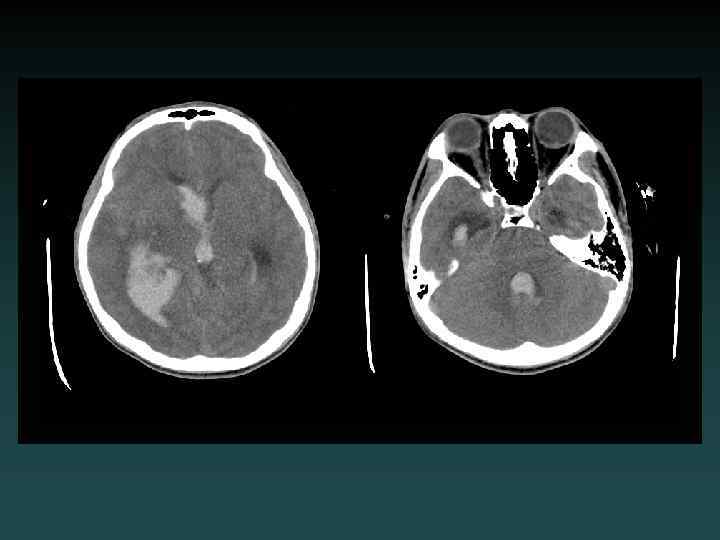

Parenchymal Hemorrhage with Ventricular Extension